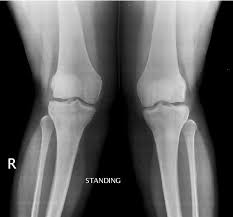

Ουσιαστικά, είναι η έσω μετατόπιση του γόνατος όταν πραγματοποιούμε διάφορες κινήσεις (τα γόνατα ενώνονται και σχηματίζουν Χ). Χαρακτηρίζεται από την προσαγωγή και έσω στροφή του ισχίου, συνήθως όταν τα ισχία βρίσκονται σε θέση κάμψης (το γόνατο, στην πραγματικότητα, απάγεται και στρέφει εξωτερικά). Πρακτικά, θα την αναγνωρίσετε όταν, για παράδειγμα, σε μια κίνηση squat (βαθύ κάθισμα), το γόνατο "βυθίζεται" προς τα μέσα. Επίσης, όταν στέκεστε στο ένα πόδι (π.χ. κατά την προσγείωσή του στη διαδικασία του τρεξίματος), η απέναντι πλευρά της λεκάνης συνήθως θα πέσει, κατά τη διάρκεια της "βύθισης" του γόνατος, στο πόδι που στηρίζεται (βλ. παρακάτω φωτογραφία).

1. Έχουν αναλογικά μεγαλύτερο εύρος ισχίων, με αντίστοιχη αύξηση της Q-γωνίας, που κάνει το ισχίο με το γόνατο (βλ. σχήμα).